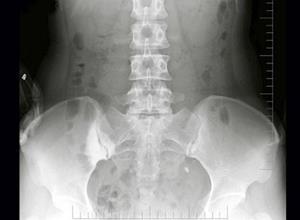

简介骶髂关节髂骨部下1/2~2/3骨质密度增厚所引起的慢性腰腿痛,称致密性髂骨炎。好发于女性,20~40岁和中年女性多见,患者有复发性下腰痛,有时可向下放射至两侧臀部和大腿,但不是根性疼痛,下腰活动时可加重症状,可能与妊娠,劳损及病灶性炎症有关。